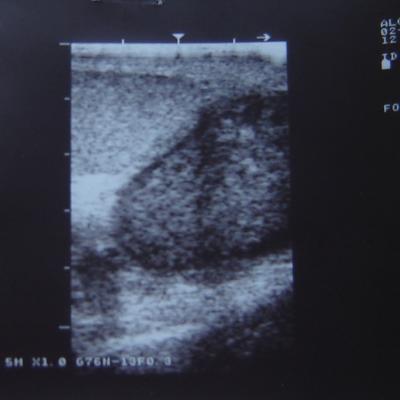

Уважаемый Алексей! По одному УЗИ не ставится диагноз. Надо сдать кровь на альфа-фетопротетеин и хореонический гонадотропин, сделать доппрерографию яичка. Проявите онконастороженность. Все лечится, если вовремя выявить. Напишите нам о результатах обследования.